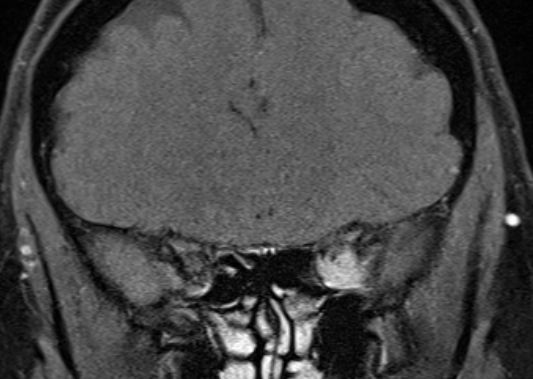

MRT eines retroorbitalen Lymphoms |